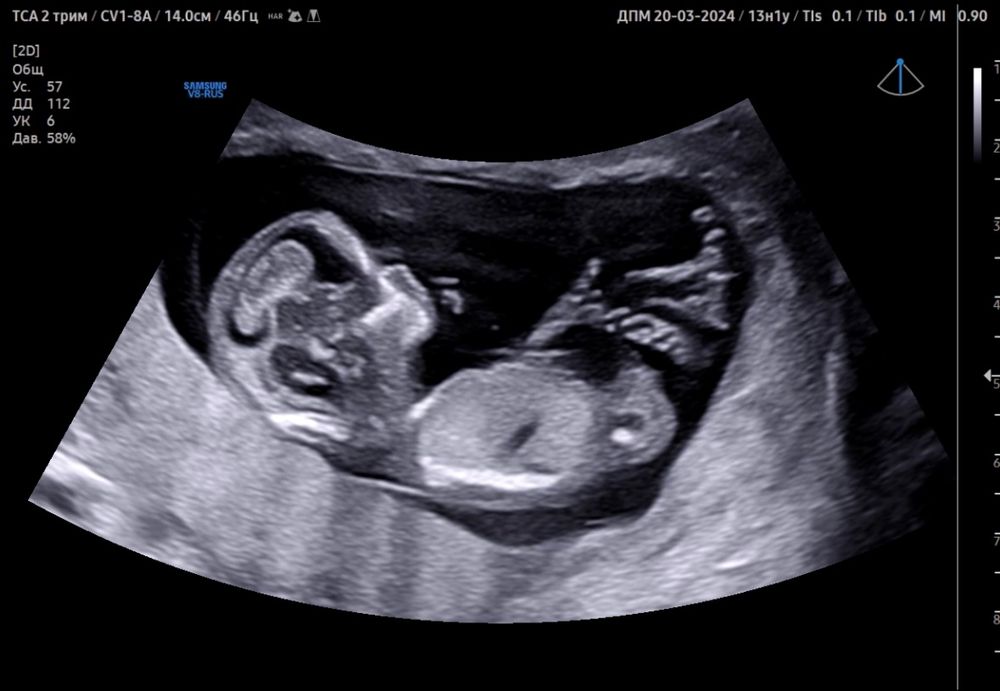

Поздравляю) это прекрасно) а где вы у Те по омс делали? Делала у него платно, прислал на почту кучу фото и видео, очень понравился как специалист. После него пошла в ЖК на скрининг и трындец просто, женщина узист грубая такая.

Наталья, не, я делала по ОМС и еще платно у Тё) наверное не так выразилась) у Тё в биопрестиже , как и в первую бер делали скрининг) мне в этот раз по ОМС повезло больше, конечно все супер быстро, но хотя бы узистка показывала сама экран и сама предложила сфотографировать, а в первый раз был ужас🙈 не врач , а ненавистник всех людей как будто была , началось все с того, что даже не удосужилась поздороваться в ответ, весь скрининг с каменным лицом ничего не показывая, не объясняя🙈

7 недель, постановка на учет Неожиданные две полоски